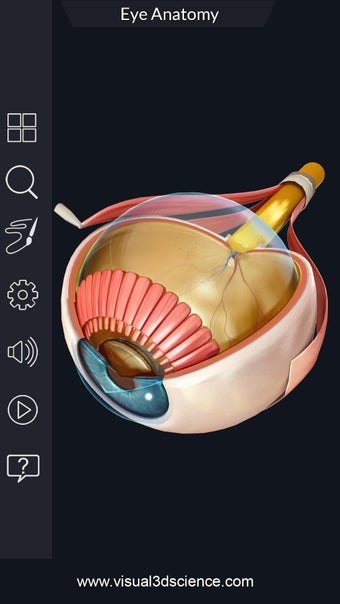

Изучите в деталях человеческий глаз и его анатомию с помощью этого простого в использовании бесплатного приложения для Android. Он позволяет масштабировать и вращать на 360° вокруг высокореалистичной 3D-модели глаза, а также рисовать на экране или прослушивать звуковое произношение каждого термина.

Вы можете выбрать X- просмотр луча, скрытие и отображение отдельных частей глаза, а также рисование или белый цвет на экране и обмен снимками экрана, звуковое произношение для всех анатомических терминов и многое другое.

Каждая часть разделена на отдельный вид, где вы можете можно увидеть название детали и ее расположение на глаз.